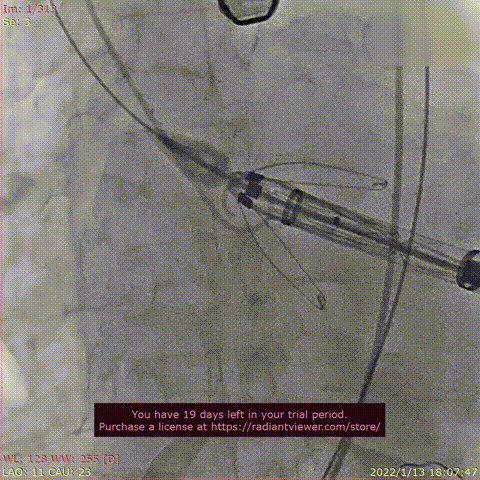

球囊域扩张

瓣膜释放过程

球囊后扩张